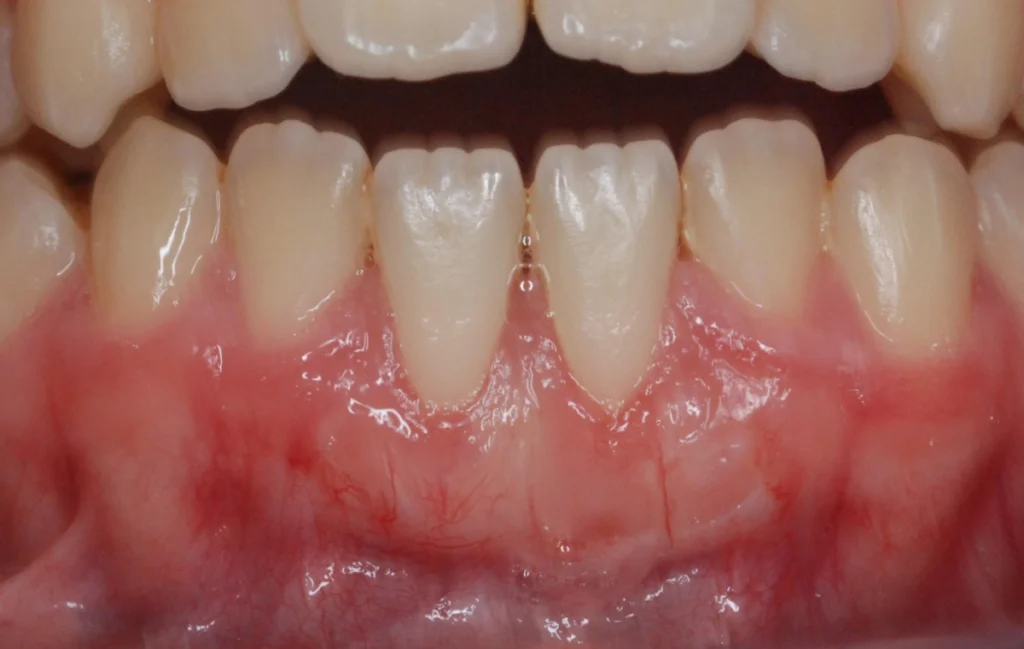

La récession gingivale

La récession gingivale est l’une des principales indications. Elle survient lorsque les gencives se rétractent, exposant les racines des dents. Cela peut être dû à un brossage agressif, à une maladie parodontale ou à un traumatisme. La chirurgie muco-gingivale couvre les racines exposées et renforce les gencives.

Cette chirurgie devient nécessaire lorsque les patients présentent des anomalies des gencives qui peuvent affecter la santé bucco-dentaire. Par exemple, la récession gingivale expose les racines des dents, augmentant le risque de caries et de sensibilité dentaire. En corrigeant ces défauts, la chirurgie muco-gingivale améliore non seulement la santé des gencives mais aussi l’esthétique du sourire.